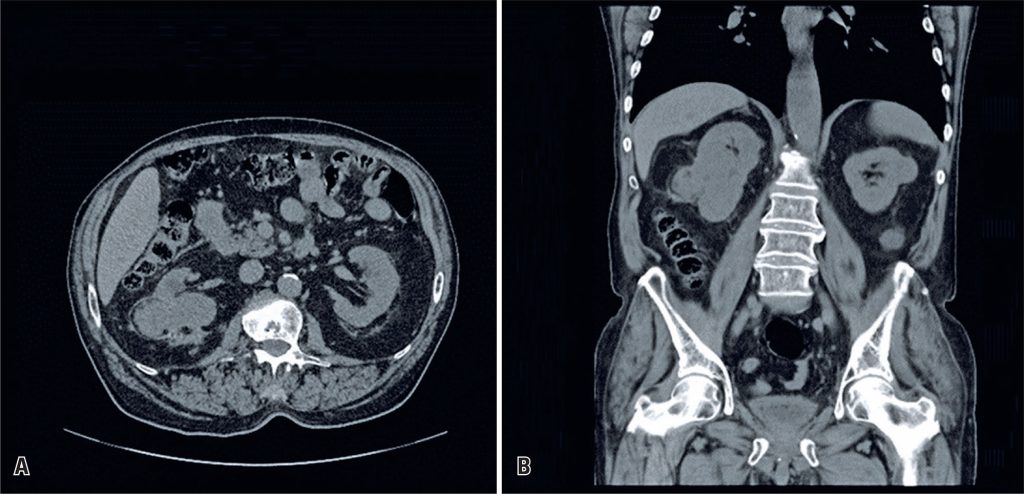

We report a case of computed tomography-guided percutaneous radiofrequency ablation of a bleeding renal angiomyolipoma. Radiofrequency ablation was performed as an alternative to partial nephrectomy and super-selective renal artery embolization for ruptured renal angiomyolipoma with slow persistent bleeding in a patient with elevated serum creatinine levels and other comorbidities. Computed tomography-guided radiofrequency ablation successfully stopped the active hemorrhage and did not affect long-term renal function during the 3-year follow period. No complications were associated with the procedure. Radiofrequency ablation of a bleeding renal angiomyolipoma may be considered a more invasive surrogate procedure in an urgent setting; however, further studies are necessary to evaluate the long-term benefits of this approach and its overall impact on renal function compared to traditional methods.